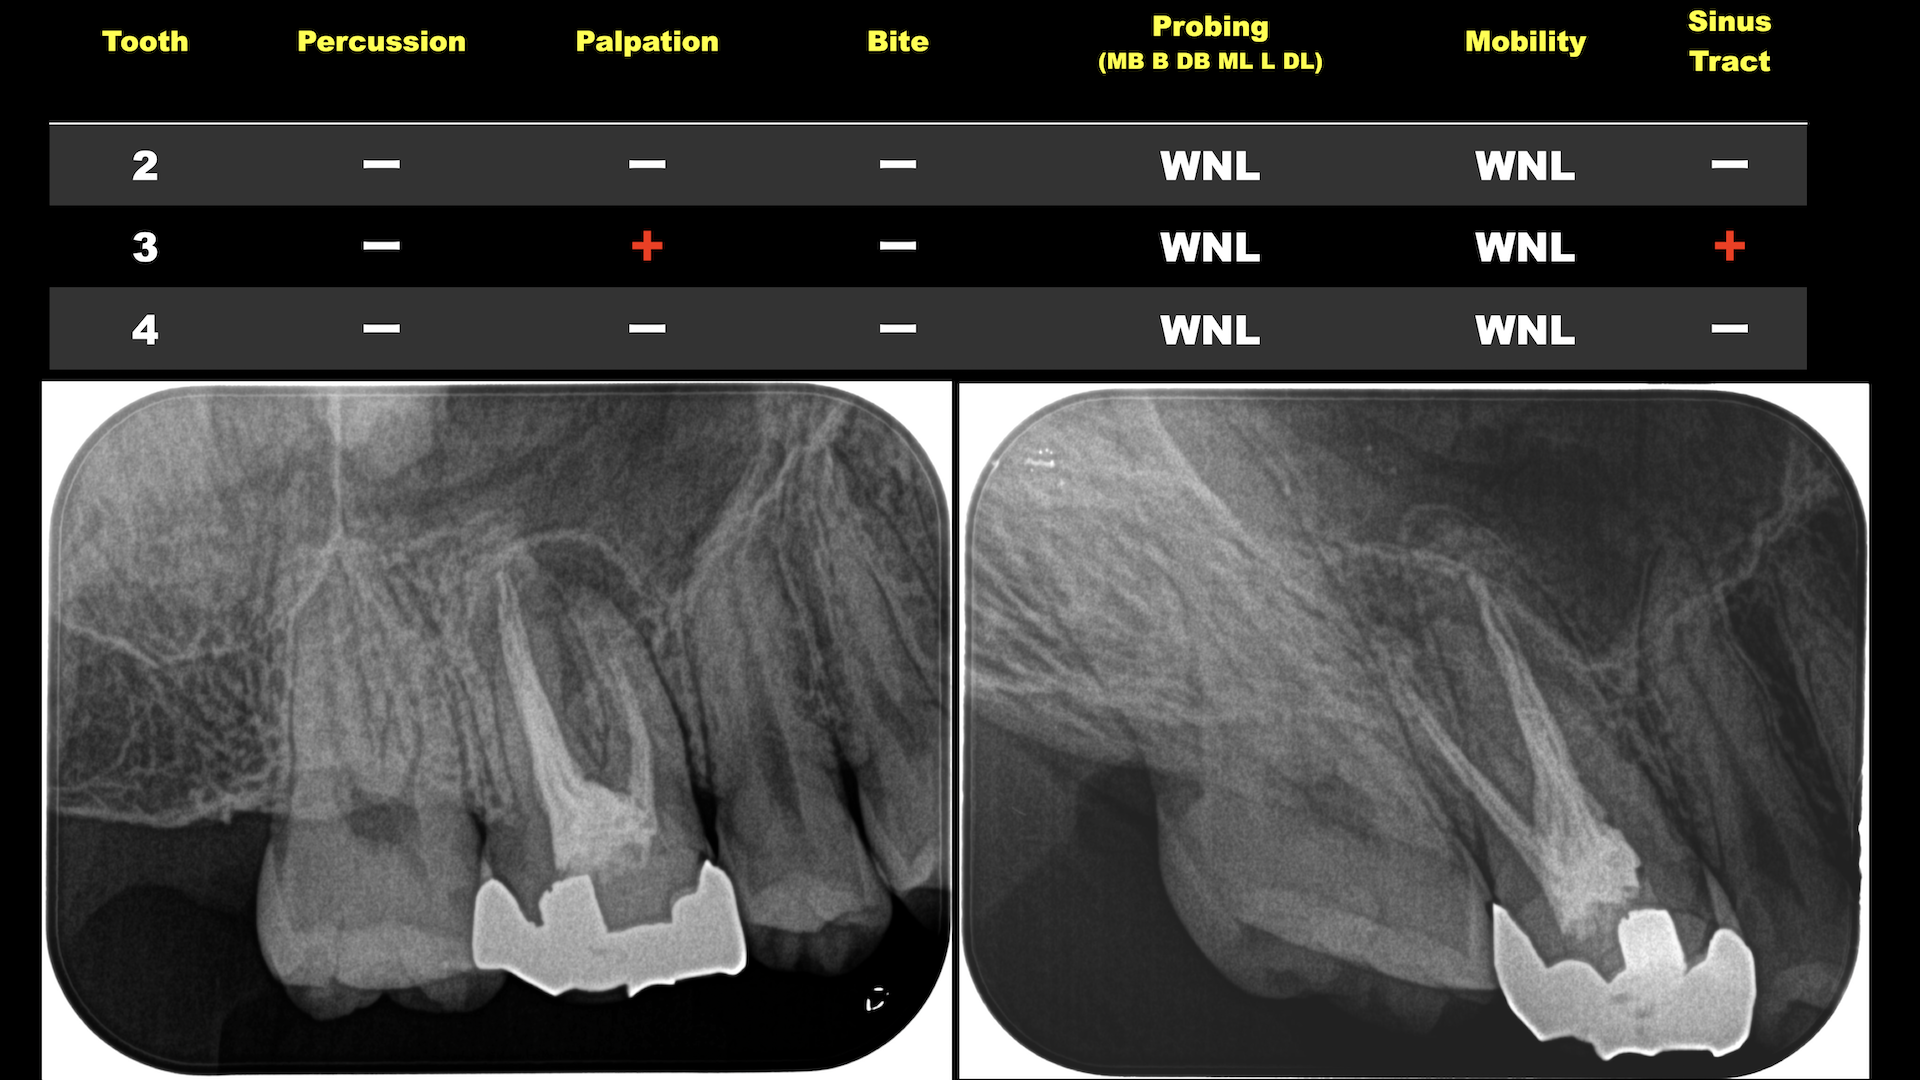

入り口はCBCTの分析以外にない、と私は考えている。

その分析方法を伝授した。